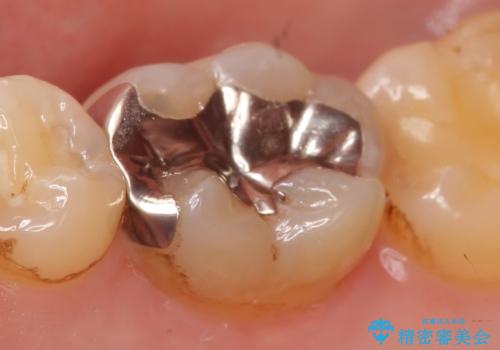

- 右下の銀歯を白くしたいといらっしゃった方の症例です。

銀歯を除去し、セラミックインレーによる修復を行いました。